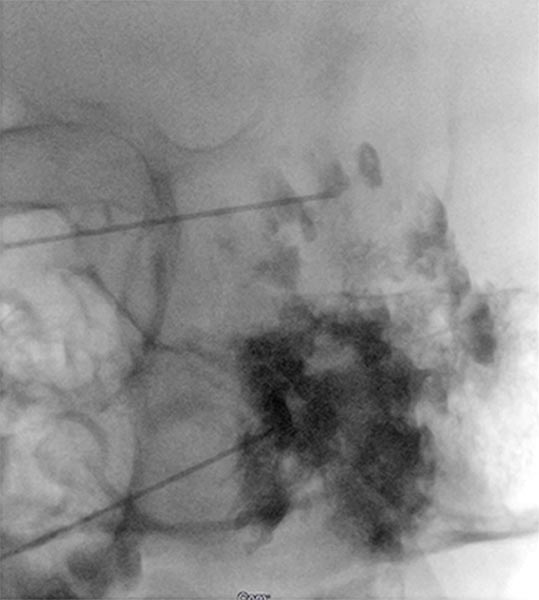

X-ray after direct injection of contrast medium into the venous malformation via 2 puncture needles. No outflow via any communication veins, good needle position for sclerotherapy. Now 2 ml of Aethoxysklerol 3% 1:4 admixed with air (foam sclerotherapy) are injected.

X-ray after injection of contrast medium into the venous malformation during the 2nd sclerotherapy 8 months later. Again no outflow via communicating veins is displayed. Good needle position for another foam sclerotherapy (3 ml Aethoxysklerol 3%, foamed 1:4 with air).

X-ray after injection of contrast medium into the venous malformation, for what is now the third sclerotherapy treatment after pain recurrence. Almost the entire remaining venous malformation is contrasted by contrast injection at the current needle position. Now 4.5 ml of Aethoxysklerol 3%, foamed 1 to 4 with air, is injected.